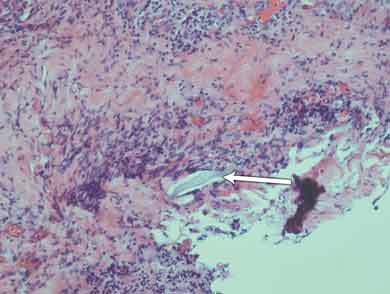

Histological results of the initial surgical specimen showed a small foreign body several microns in length intimately associated with deeply placed active inflammation (Box 1). There was fibroproliferative activity and an infiltrate of inflammatory cells; these were associated with tissue necrosis and microabscess formation. Culture of a preoperative conjunctival swab was negative for microbial growth.